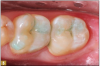

Giomer restoratives are bioactive regenerative materials that can be used where traditional direct composite materials are indicated. In the case presented in Figure 1, decay was noted on the occlusal surfaces of a first and second molar. What often looks like a very small amount of decay on the surface can lead to the discovery of significant dentin destruction. The quadrant was isolated and air abrasion was performed using 50 µm aluminum oxide (Figure 2). The occlusal groove enamel was abraded, revealing obvious decay to the dentin (Figure 3). Decay was identified with caries indicator and removed with a #2 round bur and slow-speed handpiece, with the goal of preserving as much healthy tooth structure as possible (Figure 4). Caries indicator stains denatured collagen and debris and helps to identify areas needing attention by the dentist, but equally importantly, it identifies areas without damage that can be preserved.

Fig 2. Decay was removed from the first molar, and air abrasion was performed.

Figure 2